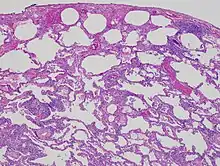

| High magnification photomicrograph of a lung biopsy taken showing chronic hypersensitivity pneumonitis (H&E), showing mild thickening of the walls of the small air sacs by invasion of white blood cells. A multinucleated giant cell, seen within the walls of the air sacs to the right of the picture halfway down, is an important clue to the correct diagnosis. | |

Lung biopsy

Lung biopsies can be diagnostic in cases of chronic hypersensitivity pneumonitis, or may help to suggest the diagnosis and trigger or intensify the search for an allergen. The main feature of chronic hypersensitivity pneumonitis on lung biopsies is expansion of the interstitium by lymphocytes accompanied by an occasional multinucleated giant cell or loose granuloma.[7][22]

When fibrosis develops in chronic hypersensitivity pneumonitis, the differential diagnosis in lung biopsies includes the idiopathic interstitial pneumonias.[23] This group of diseases includes usual interstitial pneumonia, non-specific interstitial pneumonia and cryptogenic organizing pneumonia, among others.[7][22]

The prognosis of some idiopathic interstitial pneumonias, e.g. idiopathic usual interstitial pneumonia (i.e. idiopathic pulmonary fibrosis), are very poor and the treatments of little help. This contrasts the prognosis (and treatment) for hypersensitivity pneumonitis, which is generally fairly good if the allergen is identified and exposures to it significantly reduced or eliminated. Thus, a lung biopsy, in some cases, may make a decisive difference.